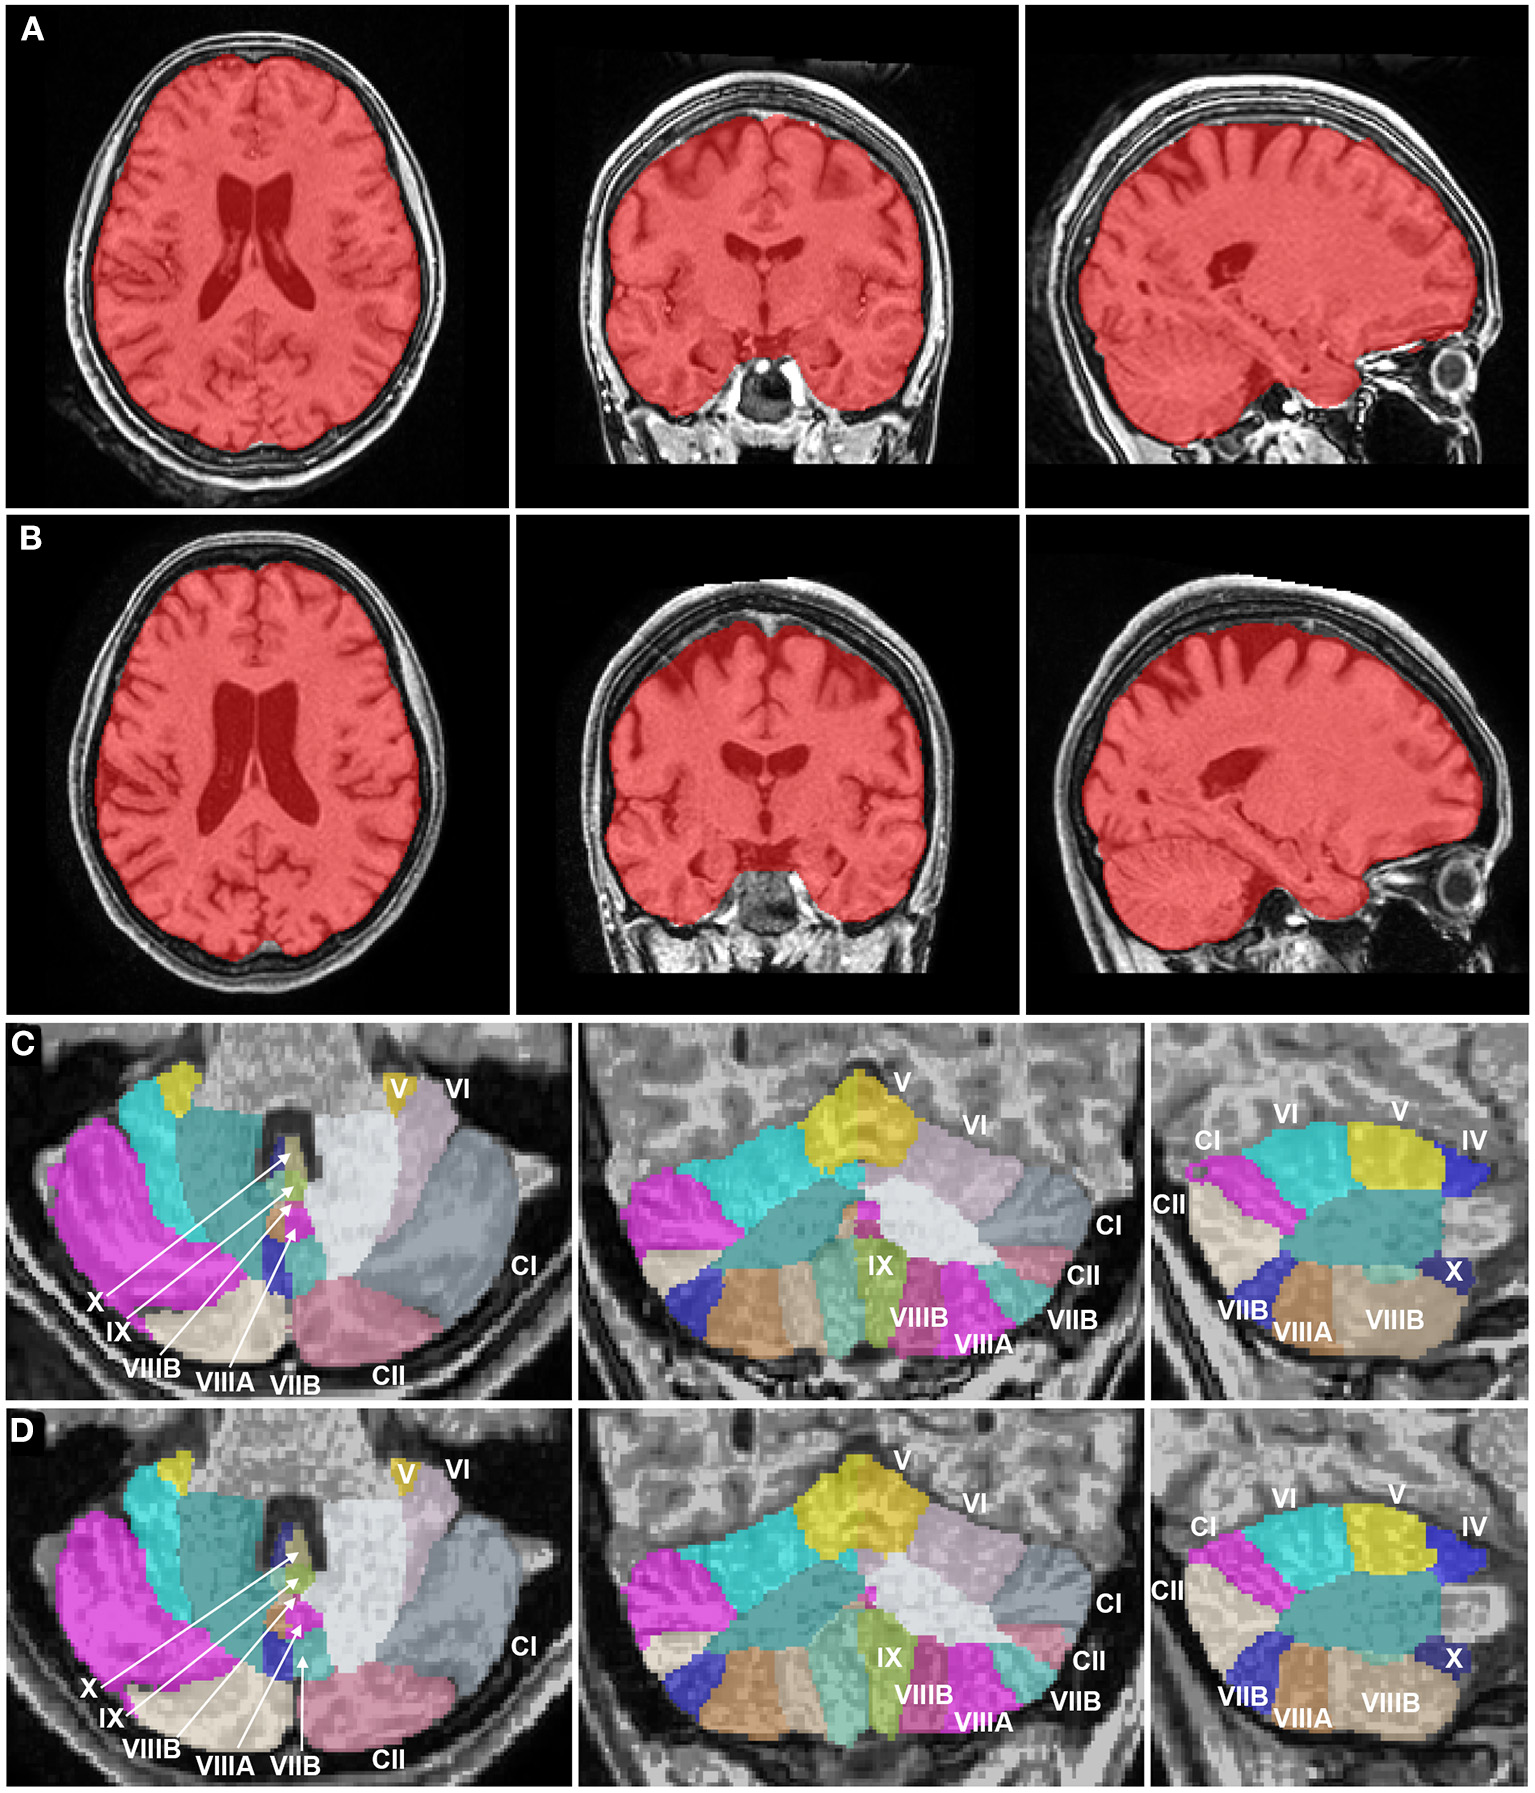

Figure 2

Brain magnetic resonance imaging segmentation maps of the patient with juvenile Huntington's disease at 18 years and 21 years. (A, B) Whole brain images (in red) of the patient in axial, coronal, and sagittal planes show an atrophy of the striatum at 18 years (A), progressing to a more diffuse process of atrophy, including subcortical structures and neocortical areas like the frontal and parietal lobes at 21 years (B). White matter volume was relatively preserved as compared to gray matter. (C, D) Cerebellum images of the patient in axial, coronal, and sagittal planes show a normal cerebellar volume and a volumetric stability at 18 years (C) and 21 years (D). The Roman numerals of the cerebellar lobules were added. CI, Crus I; CII: Crus II.

The volumes of the brain regions of the patient with adolescence-onset HD and normal controls were compared (Table 1). At 18 years of age (t1), the subcortical region was the most affected by atrophy compared to other regions (F(6, 77) = 9.99, p < 0.001). At 21 years of age, there was a more diffuse process of atrophy. The cerebellum was spared from atrophy in both t1 and t2 (Figure 1). At 18 years of age (t1), the Z-score of cerebellar volume of the patient was higher than subcortical structures and frontal lobe (cerebellum vs. subcortical region: Bonferroni mean difference = 4.67, p < 0.001; cerebellum vs. frontal lobe: Bonferroni mean difference = 2.45, p < 0.001). At 21 years of age (t2), the Z-score of cerebellar volume of the patient was higher than all other regions (F(6, 77) = 22.76, p < 0.001; cerebellum vs. subcortical region: Bonferroni mean difference = 5.21, p < 0.001; cerebellum vs. parietoocciptal lobe = 3.87, p < 0.001; cerebellum vs. limbic and insular cortex: Bonferroni mean difference = 3.45, p < 0.001 cerebellum vs. frontal lobe: Bonferroni mean difference = 3.34, p < 0.001; cerebellum vs. temporal lobe: Bonferroni mean difference = 2.46, p < 0.001). There was no marked difference in the volume of distinct lobules of cerebellum in t1 and t2 (Figure 2). There was not difference in brain region volumes between control group 1 and 2.